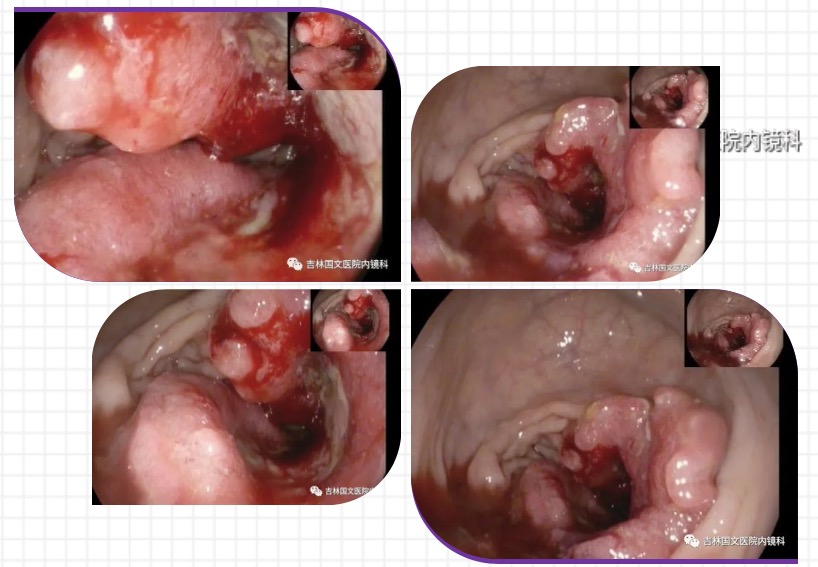

最近就有這樣一起案例,便血后自我診斷為痔瘡,當(dāng)做痔瘡治療了一年多,從未到醫(yī)院詳細(xì)檢查過(guò),近日便血加重,腸鏡檢查后,明確診斷為腸癌,被自己的無(wú)知和自以為是給害了。

借此案例,呼吁大家有癥狀一定要到正規(guī)醫(yī)院規(guī)范治療,以免延誤病情,悔恨終生!將傷害降至最低,將癌癥的種子扼殺在搖籃里。